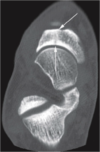

vertical fracture of lateral tibial plateau